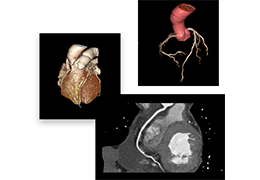

成像智能。

Eclipse 成像智能功能提供强大的处理能力和最佳质量的影像,同时减少质量错误并提高剂量效率。

凭借 AI、专有算法和先进的影像处理能力,提供出色的影像质量和无与伦比的诊断信心。

与标准影像处理相比,智能降噪功能可使客户降低辐射剂量,而不会损失影像质量。这在新生儿和儿科成像中尤其重要,在这种情况下以尽可能低的剂量成像至关重要。